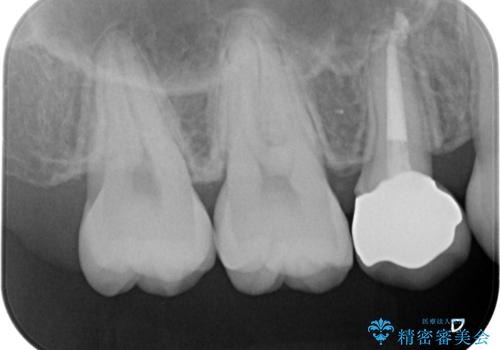

- 右上の5番目の歯の神経の治療のやり直しとセラミック治療を行いました。

- 27.4万円 内訳:精密根管治療(再治療) 12.1万円、ファイバーコア 2.2万円、仮歯 1.1万円、ジルコニアクラウン 12.1万円費用は治療当時の料金となります

術前はCRで蓋をしてあるだけでしたが、クラウンにした方が破折のリスクが少なくなります。また、根の治療がしてある歯ですが、クラウンにした方が封鎖は確実なため、長期的には有利です。また、変色の進行も外からは見えなくなりますので審美的です。